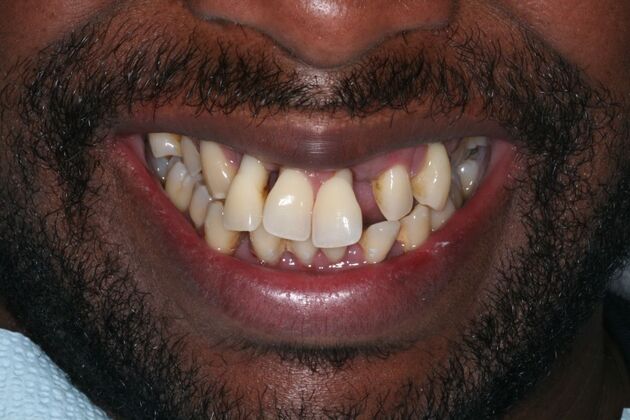

This busy business executive from NY suffered from chronic gum disease (periodontitis) due to genetics and unknown factors and had been to multiple dentists over the years and was tired of getting deep cleanings and still end up with several loose teeth in the mouth with massive bony destruction. As a young busy professional, he researched on getting the most scientific and durable treatment which could be done without several years in treatment and found Dr Bidra online. Dr. Bidra was able to successfully accomplish all his treatment goals by extracting all his teeth and installing Upper and Lower All on 4 implant bridges in 1 day. Most importantly, Dr Bidra did not need to perform any bone grafting procedures to accomplish this treatment.

Testimonial : " Dr Bidra is the best at what he does and I am so happy with my dream pearly white smile! I knew I was getting the best treatment so I did not mind driving from NY to get the best quality treatment I wanted. I highly recommend Dr Bidra and could not be happier”